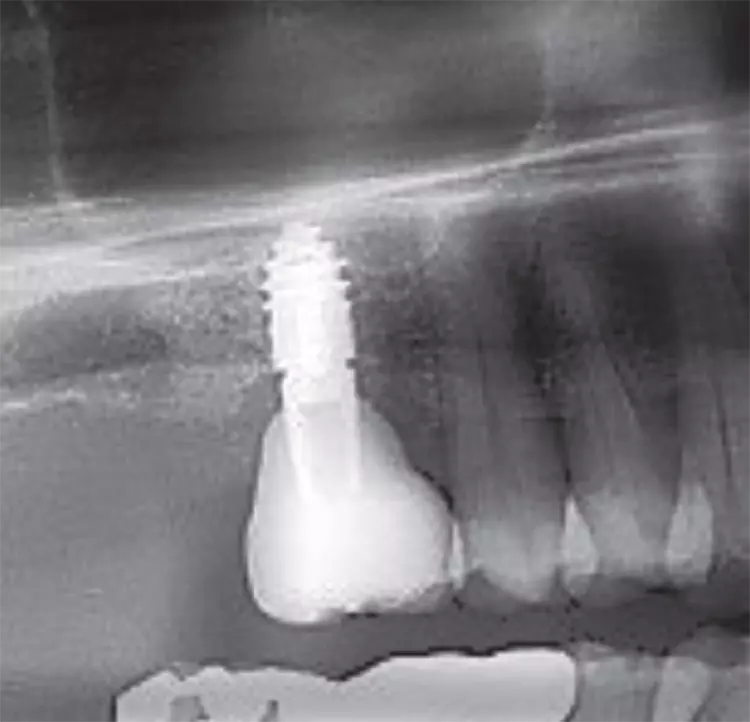

Mit dem primärstabilen WS-Condenser ø 4,3 mm wurde eine radiologische Messaufnahme durchgeführt. Dieser Fall wurde durch die neu geschaffene Kavität der IDS (interner, direkter Sinuslift) mit Smart Grinder-Material und dem im OP-Tray enthaltenen Ricci II-Instrument durchgeführt.

Gleich im Anschluss wurde ein CHAMPION (R)Evolution L 8 mm | ø 4,5 mm – ebenfalls im MIMI-Verfahren – mit einer Primärstabilität von 40 Ncm inseriert. Das DVT zeigt sehr deutlich die „weiße Wolke“ des Grinder-Materials, welches mehr Knochenwachstumsfaktoren enthält als Knochen selbst und durch die Schneider‘sche Membran optimal ernährt wird. Am gleichen Operationstag erfolgte die geschlossene Abformung samt Bissnahme (Abb. 20-23).